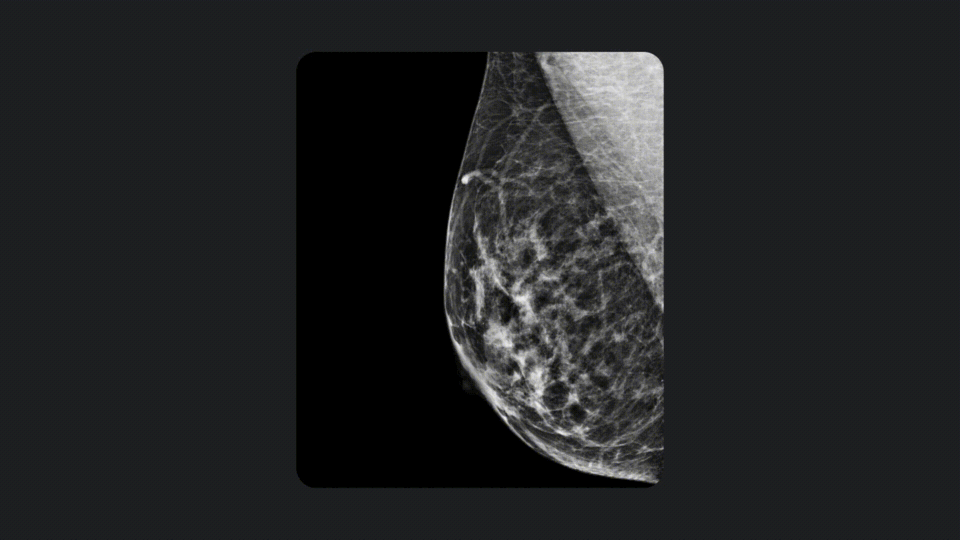

구글은 지난 10년 동안 AI를 활용한 의료 이미징 기술을 개발해왔으며, 유방암, 폐암, 당뇨망막병증 등의 질병을 조기에 감지할 수 있는 AI 시스템을 구축했다고 합니다. 현재 인도와 태국에서는 구글의 AI를 활용해 600만 건 이상의 당뇨망막병증 검사를 무료로 제공할 계획이며, 인도의 Apollo Radiology International은 결핵, 폐암, 유방암을 포함한 300만 건의 무료 검사를 제공한다고 발표했습니다.